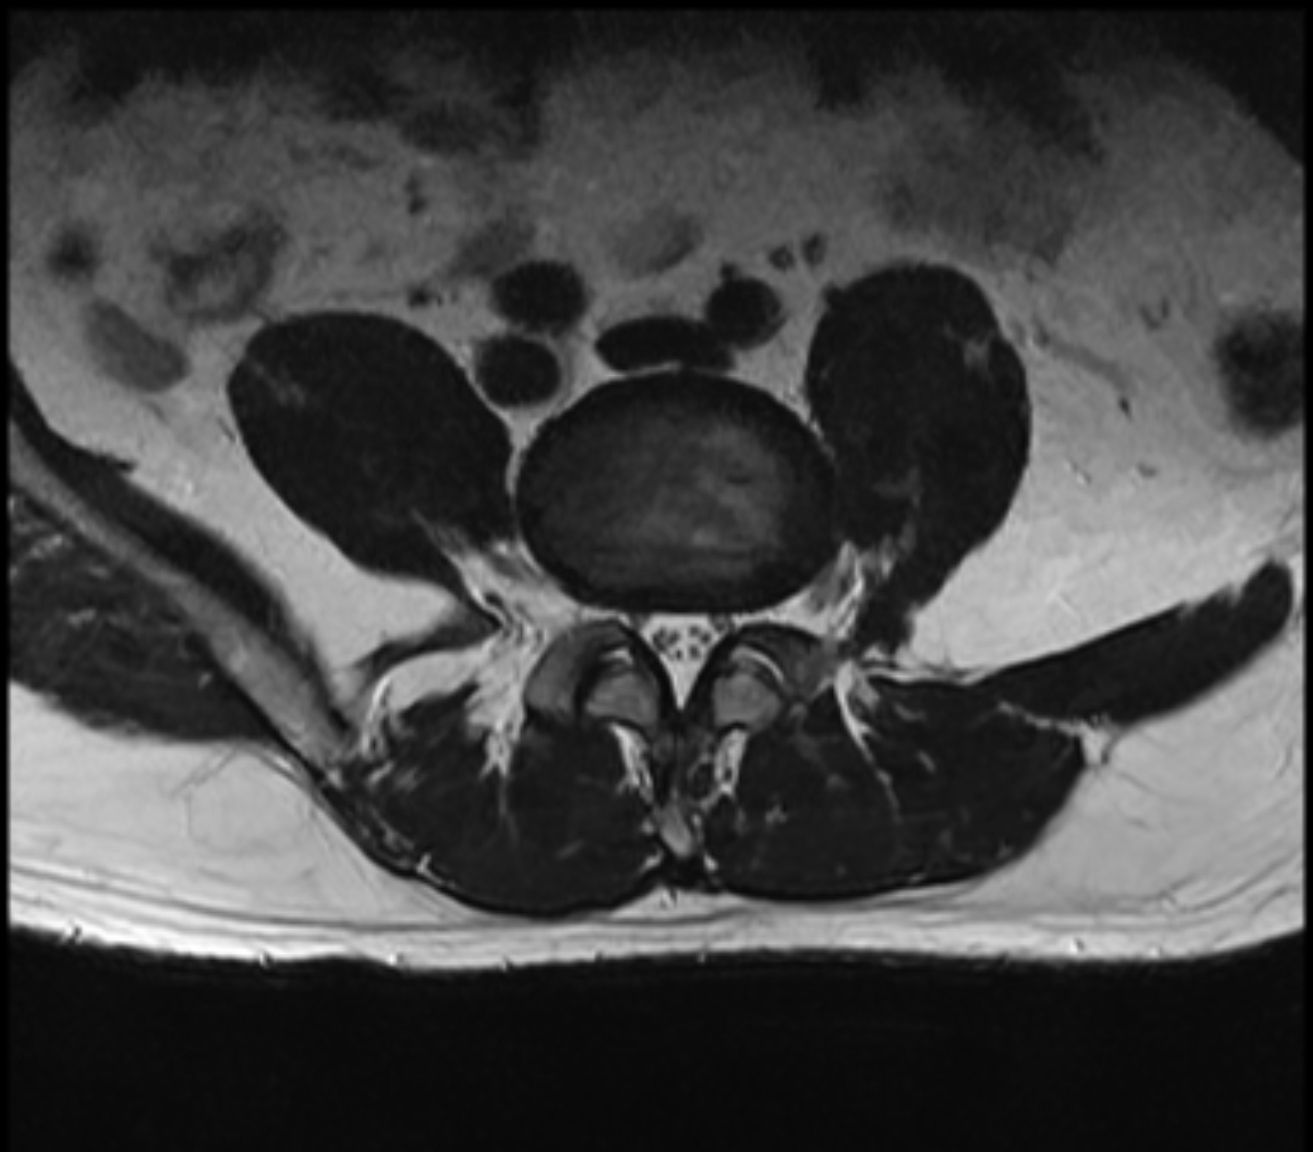

MR报告

放射学表现

腰椎生理曲度变直 , 椎体排列尚整齐 ; 腰3椎体偏前侧见 0.9x 1.4cm的椭圆形较高信号灶 , 压脂后信号减低 , 余所示 椎体信号未见明显异常 , 各椎体边缘骨质增生改变 , 骨性 椎管未见明显狭窄 ; 腰5/聶1椎间隙变窄 , 相对缘终板面略 毛糙 , T2WI/FS信号稍高 ; 腰5/髓1椎间盘向后明显突出 致局部椎管变窄 , 马尾终丝受压 ; 腰3/4、4/5水平椎间盘 向周围轻度膨隆 , 硬膜囊略受压 ; 余圆锥、马尾形态、信 号未见明显异常。

放射学诊断

1.腰5/艇1椎间盘明显突出 , 致局部椎管变窄。 2.腰3/4、 4/5椎间盘轻度膨隆。 3.腰3椎体异常信号灶 , 考虑脂肪沉 积可能 , 请随诊。 4.腰椎轻度退变 , 生理曲度变直 ; 腰5/ 融1椎体相对缘终板炎改变。